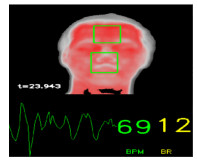

• 摘要: 针对目前临床上监测生命体征设备的不便携带、接触人体等问题实现了一种将红外热成像仪作为信息采集设备,通过分析人体面部血管模型及鼻孔位置温差变化得到心率值和呼吸信息的方法。首先对获取的热像图序列提取前景目标以缩短在整幅图像中进行人脸检测的时间,再利用各向异性扩散滤波法增强感兴趣区域内血管位置的对比度,并利用形态学处理获得人脸血管部位的灰度均值形成初始心率信号。最终通过趋势消除、小波阈值去噪方法去除时间序列中的趋势项和随机噪声获取最终的心率波形图和动态心率、呼吸值。与医院专用设备对比试验得出该方法可控制心率误差小于4%,平均的均值误差为 \left| \bar d \right| =0.718次/min。呼吸误差在1次/min内,具有较高的准确性和鲁棒性,能够满足实际需求。

Abstract: To solve the problems of inconvenient carrying and contact with the human body when using current clinical vital signs monitoring equipment, a method of estimating heart rate and respiratory information is proposed by analyzing the facial vascular model and temperature difference of the nostril position using an infrared thermal imager as a transmission device. First, the foreground target is extracted from the obtained thermal image sequence to shorten the time of face detection in the entire image. Anisotropic diffusion is then used to enhance the contrast of the vascular position in the region of interest, and the gray mean of the vascular position in the face is obtained by morphological processing to form the initial heart rate signal. Finally, trend elimination, wavelet threshold denoising, and other filtering methods were used to remove the trend item and random noise in the time series to obtain the final heart rate waveform, dynamic heart, and respiration values. Compared with specialized equipment in the hospital, it was found that the method exhibited a heart rate error of less than 4%, and the average error of the average value was 0.718 beats/min. The breathing error is within 1 beat/min, showing high accuracy and robustness and that the method can meet actual needs.